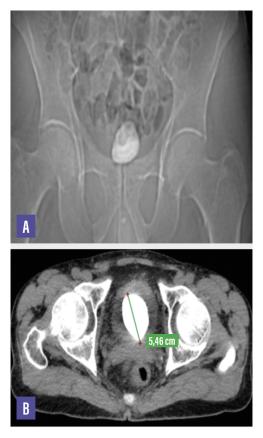

Une radiographie de l’abdomen sans préparation centrée sur le bassin montre une opacité de tonalité calcique occupant l’aire vésicale (fig. A). Un scanner abdomino-pelvien sans injection de produit de contraste est réalisé afin de mieux analyser cette masse  ; il permet de visualiser une lithiase vésicale occupant la quasi-totalité de la vessie et mesurant 55 × 45 mm avec 1 120 UH de densité (fig. B).